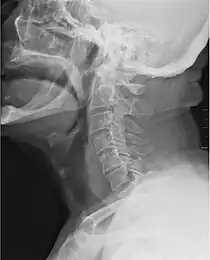

![]() X-ray showing the throat, seen as a dark band to the front of the spine | |